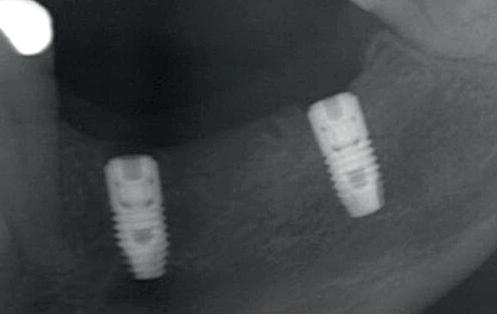

Bij klinisch en röntgenologisch onderzoek viel echter op dat radix van de 12 en 22 een convergerende (de radices staan dan naar mesiaal en naar elkaar toe) in plaats van divergerende (radices staan dan van elkaar af) stand had. Door deze convergerende stand van de radices was er in mesio-distale zin geen ruimte voor twee implantaten ter plaatse van de 11 en 21. Er werd daarom besloten, in tegenzin

1. Retainer met twee frontelementen

2. OPT radices 12 en 22 convergeren

4. OPT radices 12 en 22 divergeren na orthodontische behandeling

van de patiënt, om eerst weer vaste apparatuur terug te plaatsen om de radices in een divergerende stand te plaatsen. Gelukkig verliep deze behandeling voorspoedig. (afbeelding 2 -4). Het volgende behandelplan werd gemaakt: